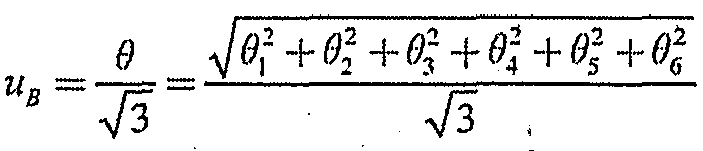

6.4. Стандартную неопределенность, обусловленную присутствием не исключенных остатков систематических погрешностей, %, вычисляют по формуле:

, где

, где

(8)

- границы систематической погрешности результата измерения для Р = 0,95, состоящей из:

- границы систематической погрешности результата измерения для Р = 0,95, состоящей из:

- основная относительная погрешность согласно ТД на используемое средство измерения, %;

- основная относительная погрешность согласно ТД на используемое средство измерения, %;

- дополнительная относительная погрешность, вызванная энергетической зависимостью, или погрешность определения поправочного множителя, зависящего от энергии излучения, определенная при поверке, %;

- дополнительная относительная погрешность, вызванная энергетической зависимостью, или погрешность определения поправочного множителя, зависящего от энергии излучения, определенная при поверке, %;

- дополнительная относительная погрешность, обусловленная анизотропией чувствительности средства измерения в пределах углов

- дополнительная относительная погрешность, обусловленная анизотропией чувствительности средства измерения в пределах углов  90, % (из ТД на используемое средство измерения);

90, % (из ТД на используемое средство измерения);

- дополнительная относительная погрешность, вызванная отличием температуры воздуха от указанной в ТД на используемое средство измерения;

- дополнительная относительная погрешность, вызванная отличием температуры воздуха от указанной в ТД на используемое средство измерения;

- дополнительная относительная погрешность, вызванная отличием влажности воздуха от указанной в ТД на используемое средство измерения;

- дополнительная относительная погрешность, вызванная отличием влажности воздуха от указанной в ТД на используемое средство измерения;

- дополнительная относительная погрешность, вызванная отличием спектра излучения при калибровке (поверке) дозиметра и при проведении измерений, (

- дополнительная относительная погрешность, вызванная отличием спектра излучения при калибровке (поверке) дозиметра и при проведении измерений, ( = 5 - 8 %).

= 5 - 8 %).